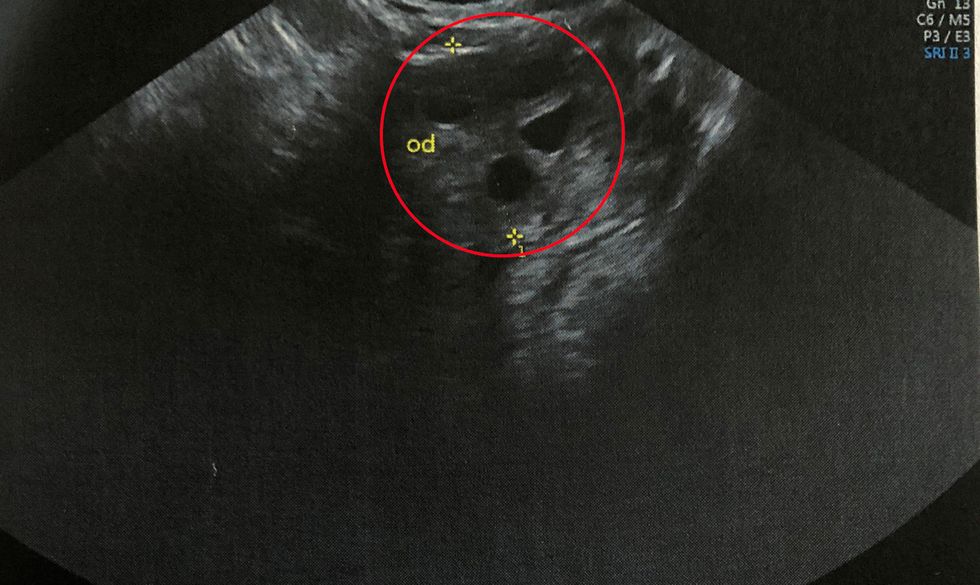

“At a check-up, they said my levels had risen, so I had an ultrasound scan at Hospital Quirón Torrevieja, in Alicante, a private hospital, to be seen quicker and a growth was spotted.”

“Looking at the scan on the screen, I could see the tumor. It was like a cluster of grapes and doctors believed a small amount had continued to grow after the first tumor was removed.”